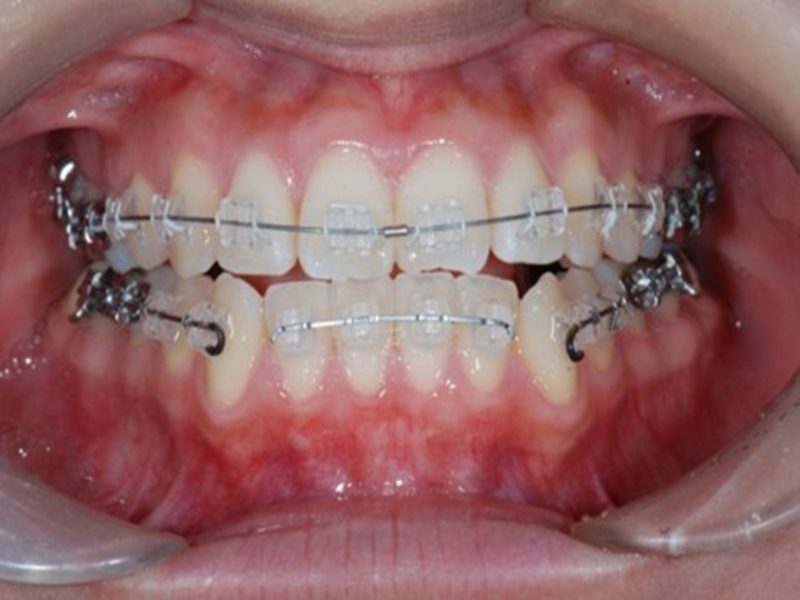

経過